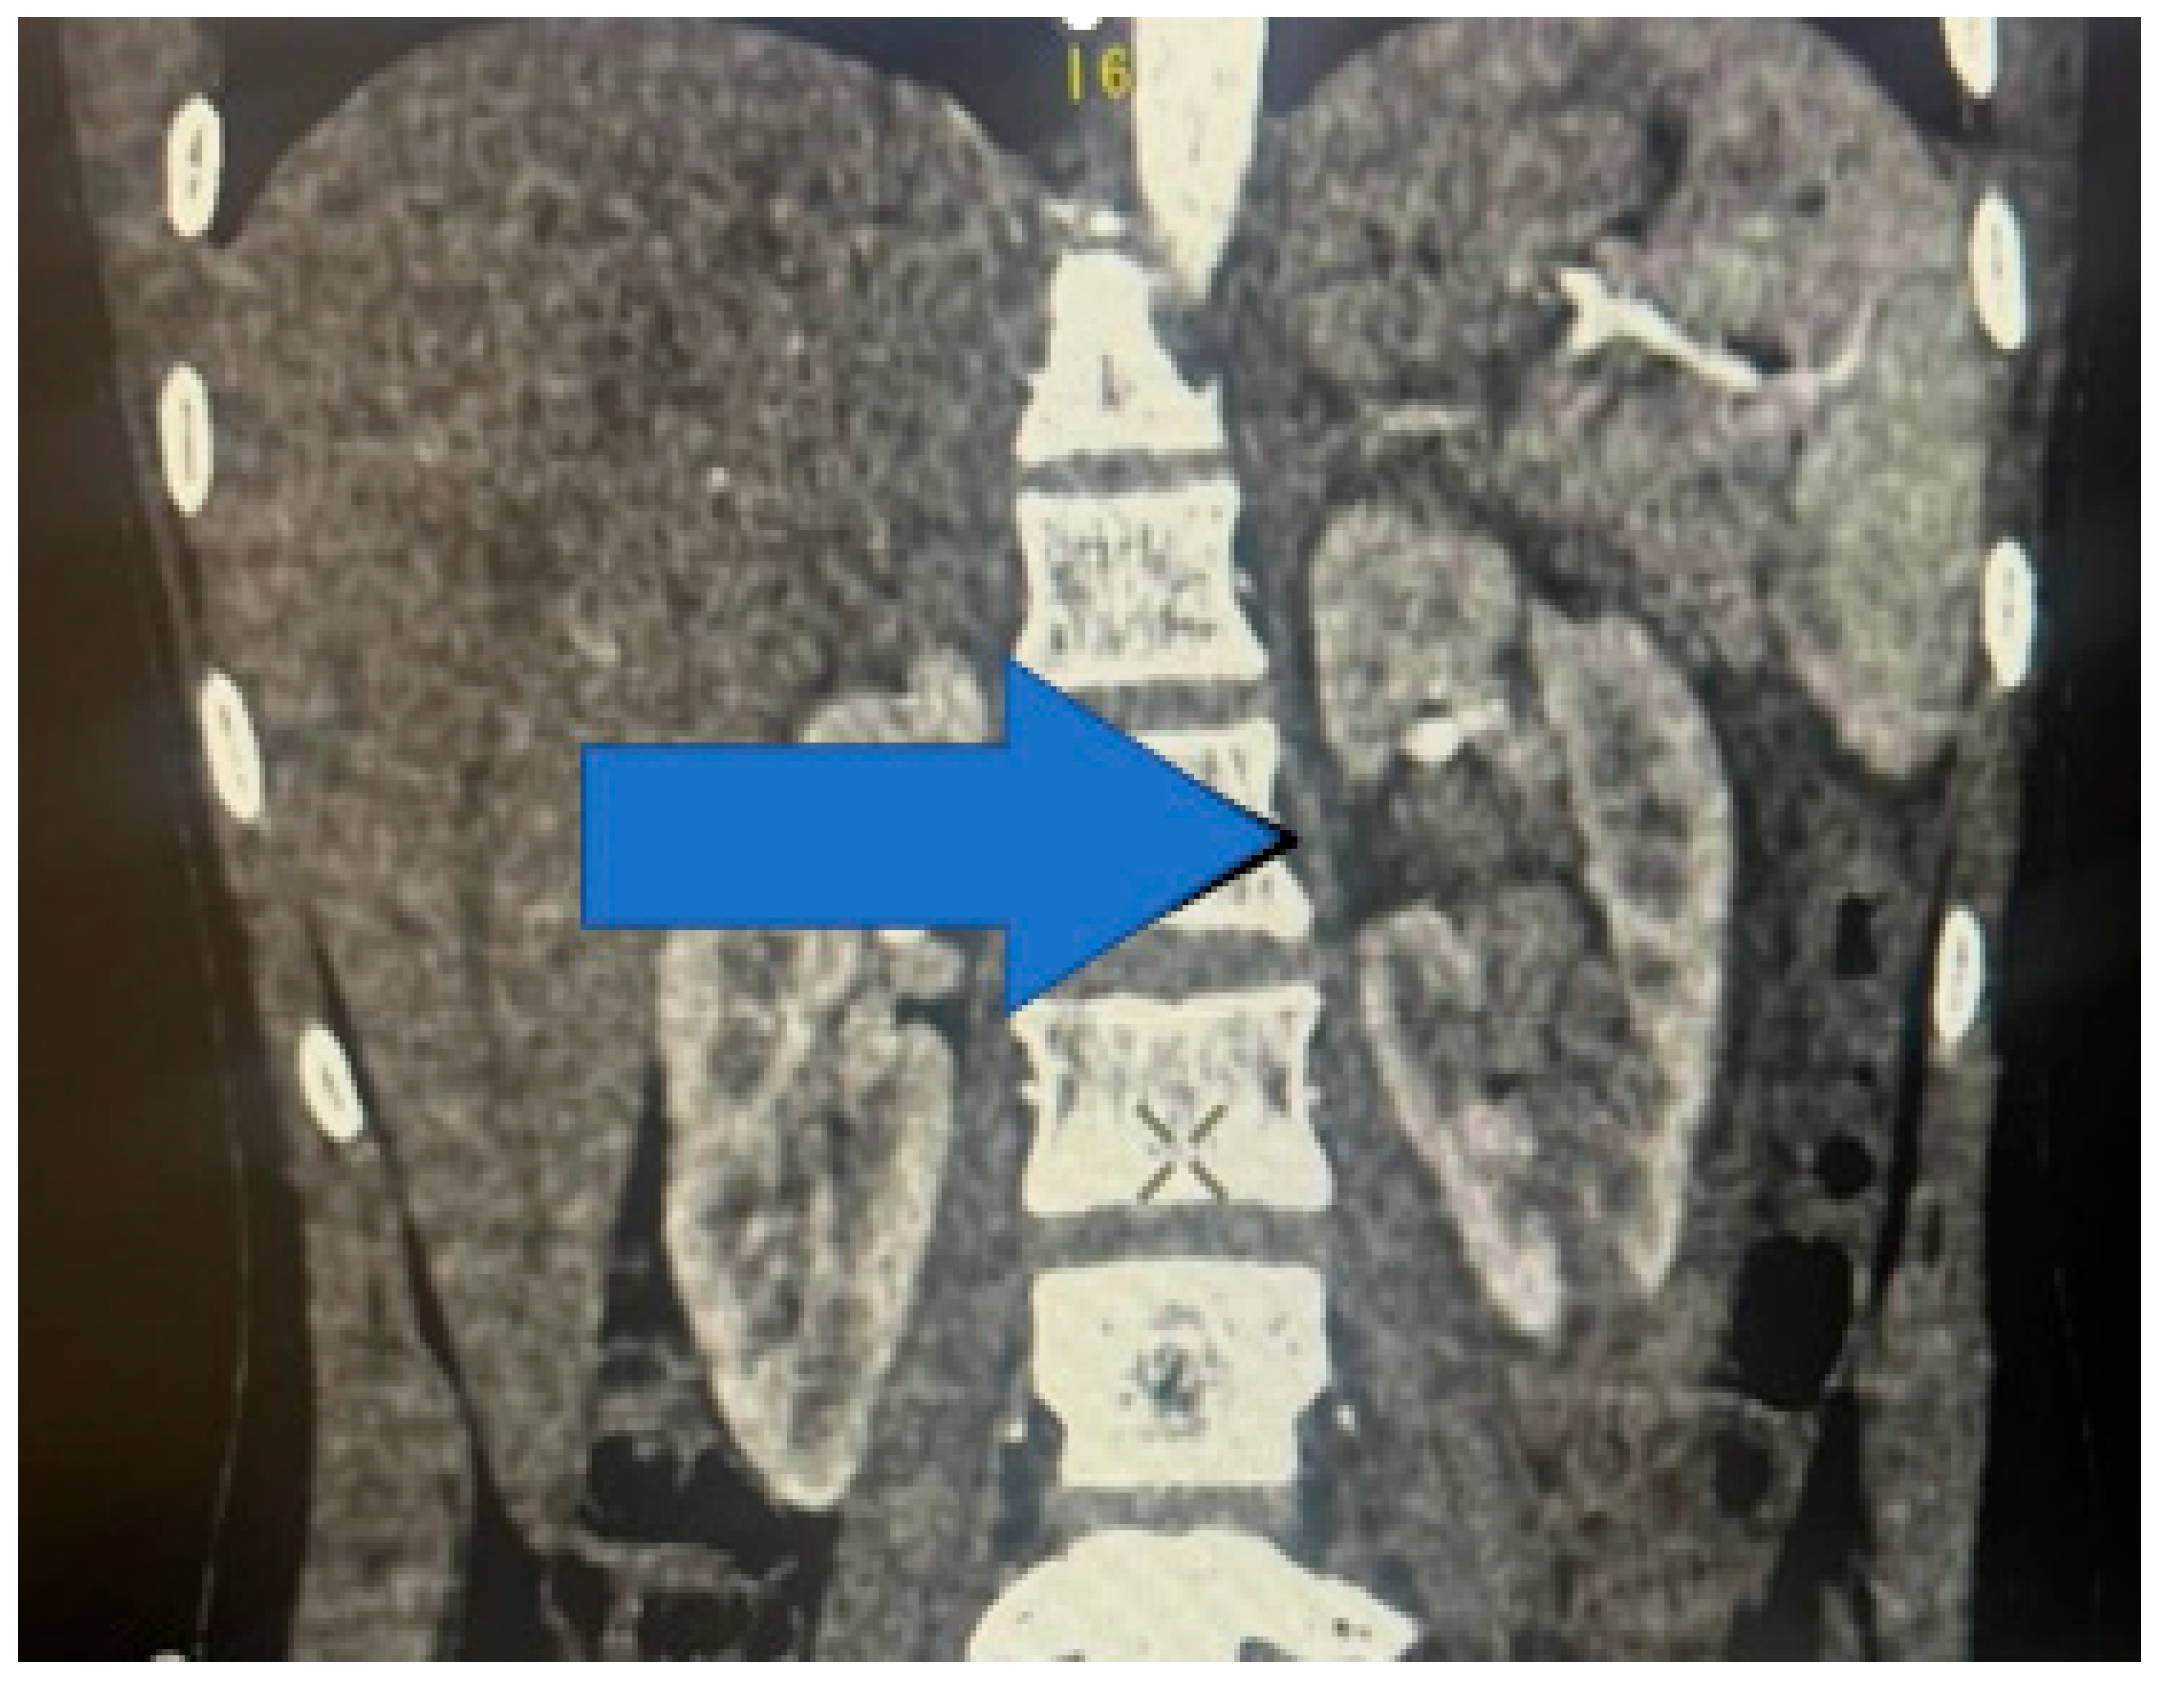

The distribution of the renal injuries, according to AAST classification (Figure 5), in this study is the following: grade 1 (Figure 6) (26.97%), grade 2 (Figure 7) (34.83%), grade 3 (Figure 8) (19.10%), grade 4 (Figure 9) (10.11%), and grade 5 (Figure 10 and Figure 11) (8.99%).

Figure 11. Contrast-enhanced CT scan showing left-kidney grade 5 injury—avulsion of renal hilum with large hematoma, coronal section.